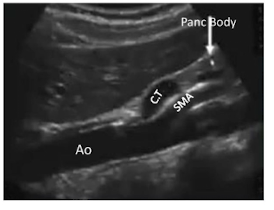

Be able to identify this image taken in a transverse plane

The pancreas sits horizontally in the abdominal cavity so in order to get a long axis image the sonographer must scan in the __________ plane

Transverse